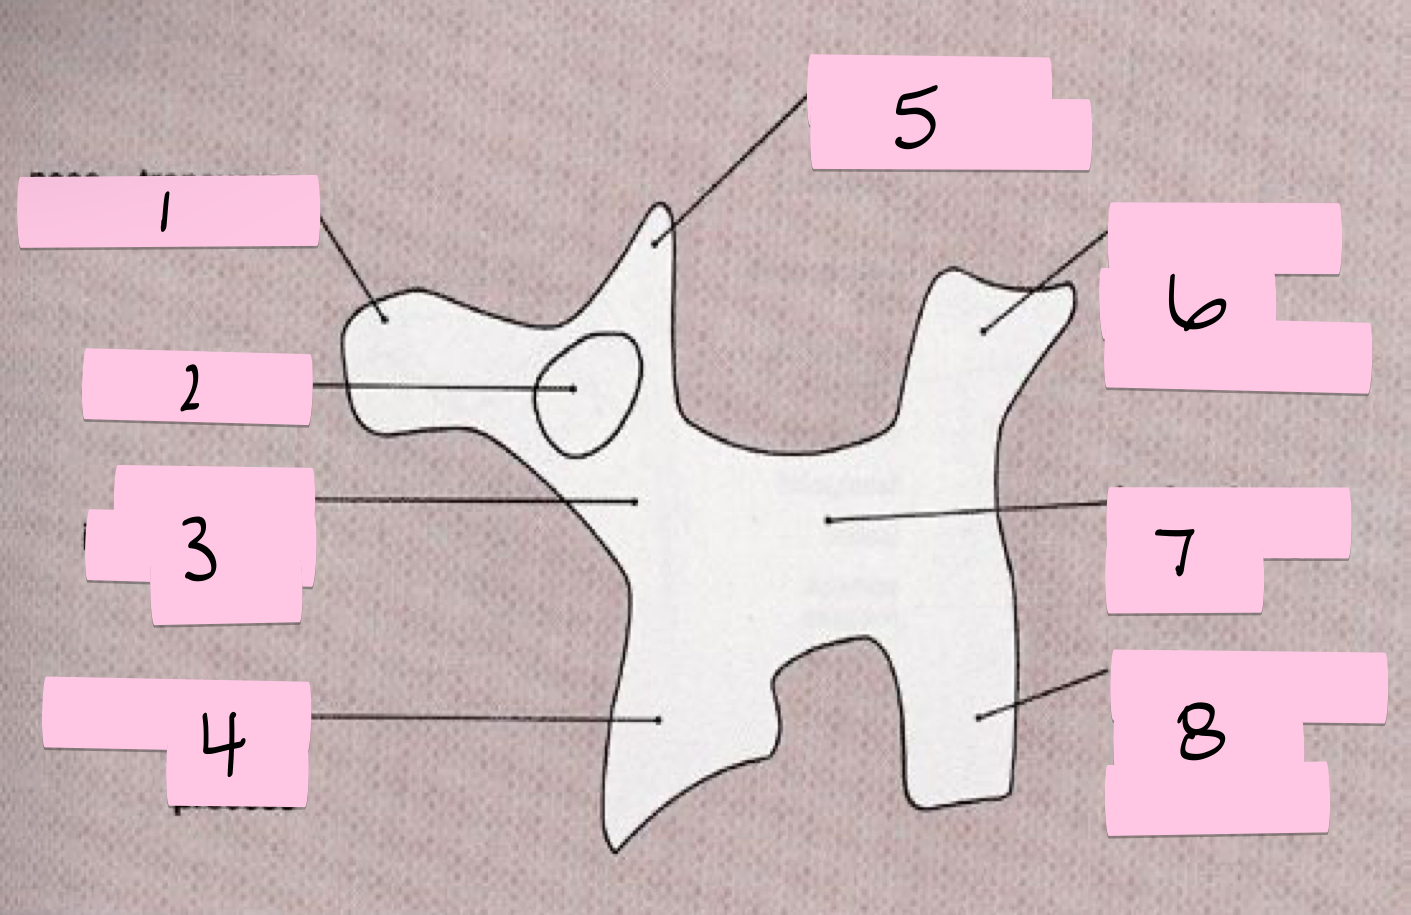

What is 1 pointing to?

Nose- Transverse process

What is 2 pointing to?

Eye- Pedicle

What is 3 pointing to?

Neck- Pars interacticularis (isthmus)

What is 4 pointing to?

Foreleg- Inferior articular process

What is 5 pointing to?

Ear- Superior articular process

What is 6 pointing to?

Tail- Superior articular process of opposite side

What is 7 pointing to?

Body- Lamina and spinous process

What is 8 pointing to?

Hindleg- Inferior articular process of opposite side